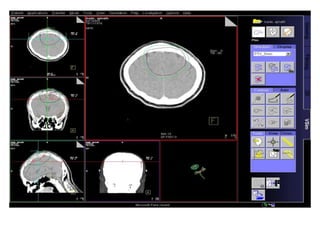

RT planning: meningioma

GTV/CTV = residual tumour / tumour bed for gr II / gr III

CTV = 5 mm for benign meningiomas

2 - 3 cms for high grade meningiomas / HPC

PTV = 2mm for SRT

5mm for 3DCRT

All normal structures contoured

Dosage:

Gr-I:

54Gy/30# conformal RT

25Gy/5# / 13Gy/1#

Gr II & III meningioma:

60Gy/30#/6wks

Conformal RT

Grade I Grade II/III

Tharmoplastic mask

CT scan with contrast- 3 mm slice

MRI scan with T1 contrast & T2 flair is a must

RT planning: meningioma GTV/CTV= residual tumour / tumour bed for gr II / gr III CTV = 5 mm for benign meningiomas 2 - 3 cms for high grade meningiomas / HPC PTV = 2mm for SRT 5mm for 3DCRT All normal structures contoured Dosage: Gr-I: 54Gy/30# conformal RT 25Gy/5# / 13Gy/1# Gr II & III meningioma: 60Gy/30#/6wks Conformal RT Grade I Grade II/III Tharmoplastic mask CT scan with contrast- 3 mm slice MRI scan with T1 contrast & T2 flair is a must